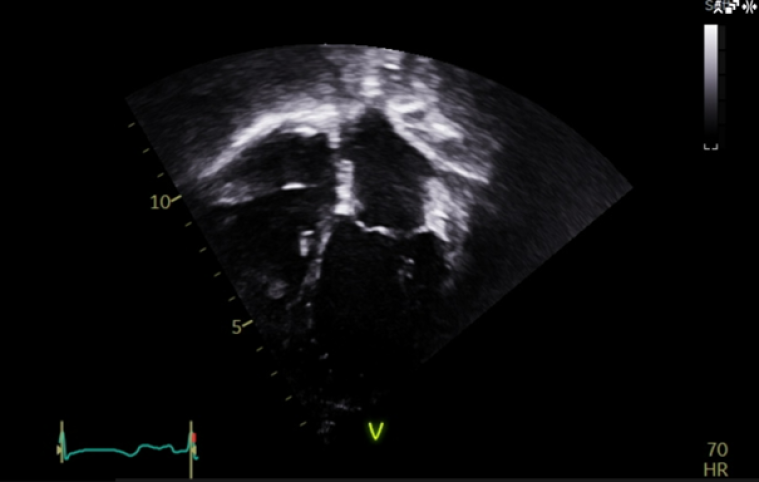

At the age of 4 years, the patient started developing a distinct echocardiographic phenotype (Image 5), with a dilated left atrium (LA) (LA area 12.1 cm3, z score +5.7) and right atrium (RA) (RA area 10.8 cm3, z score +4.1), preserved global left ventricular systolic function, but impaired longitudinal function (tissue doppler lateral S’ wave 0.07m/s, septal 0.05m/s) and evidence of early impaired left ventricular relaxation (isovolumetric relaxation time 114ms, pulmonary vein A-wave duration 166msm abnormal mitral valve doppler). The left ventricle itself was normal in size, with a maximal wall thickness of 5-6mm (z score +02), with no significant valvular or other abnormalities.